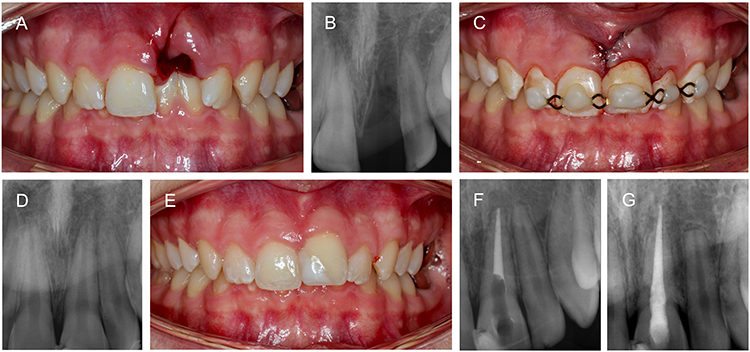

Bei Zähnen mit unreifen Wurzeln ist dagegen eine Revaskularisation möglich [13,57]. Nach Abschluss der Akuttherapie richtet sich die weitere Behandlung nach dem Stadium des Wurzelwachstums und der Lagerung des Zahnes bis zur Replantation. Da nach einer Avulsion wurzelreifer Zähne unabhängig von den Lagerungsbedingungen mit einer Pulpanekrose gerechnet werden muss, ist die Einleitung einer unmittelbaren endodontischen Behandlung innerhalb einer Woche indiziert (Abb. 5).

Prof. Dr. Widbiller